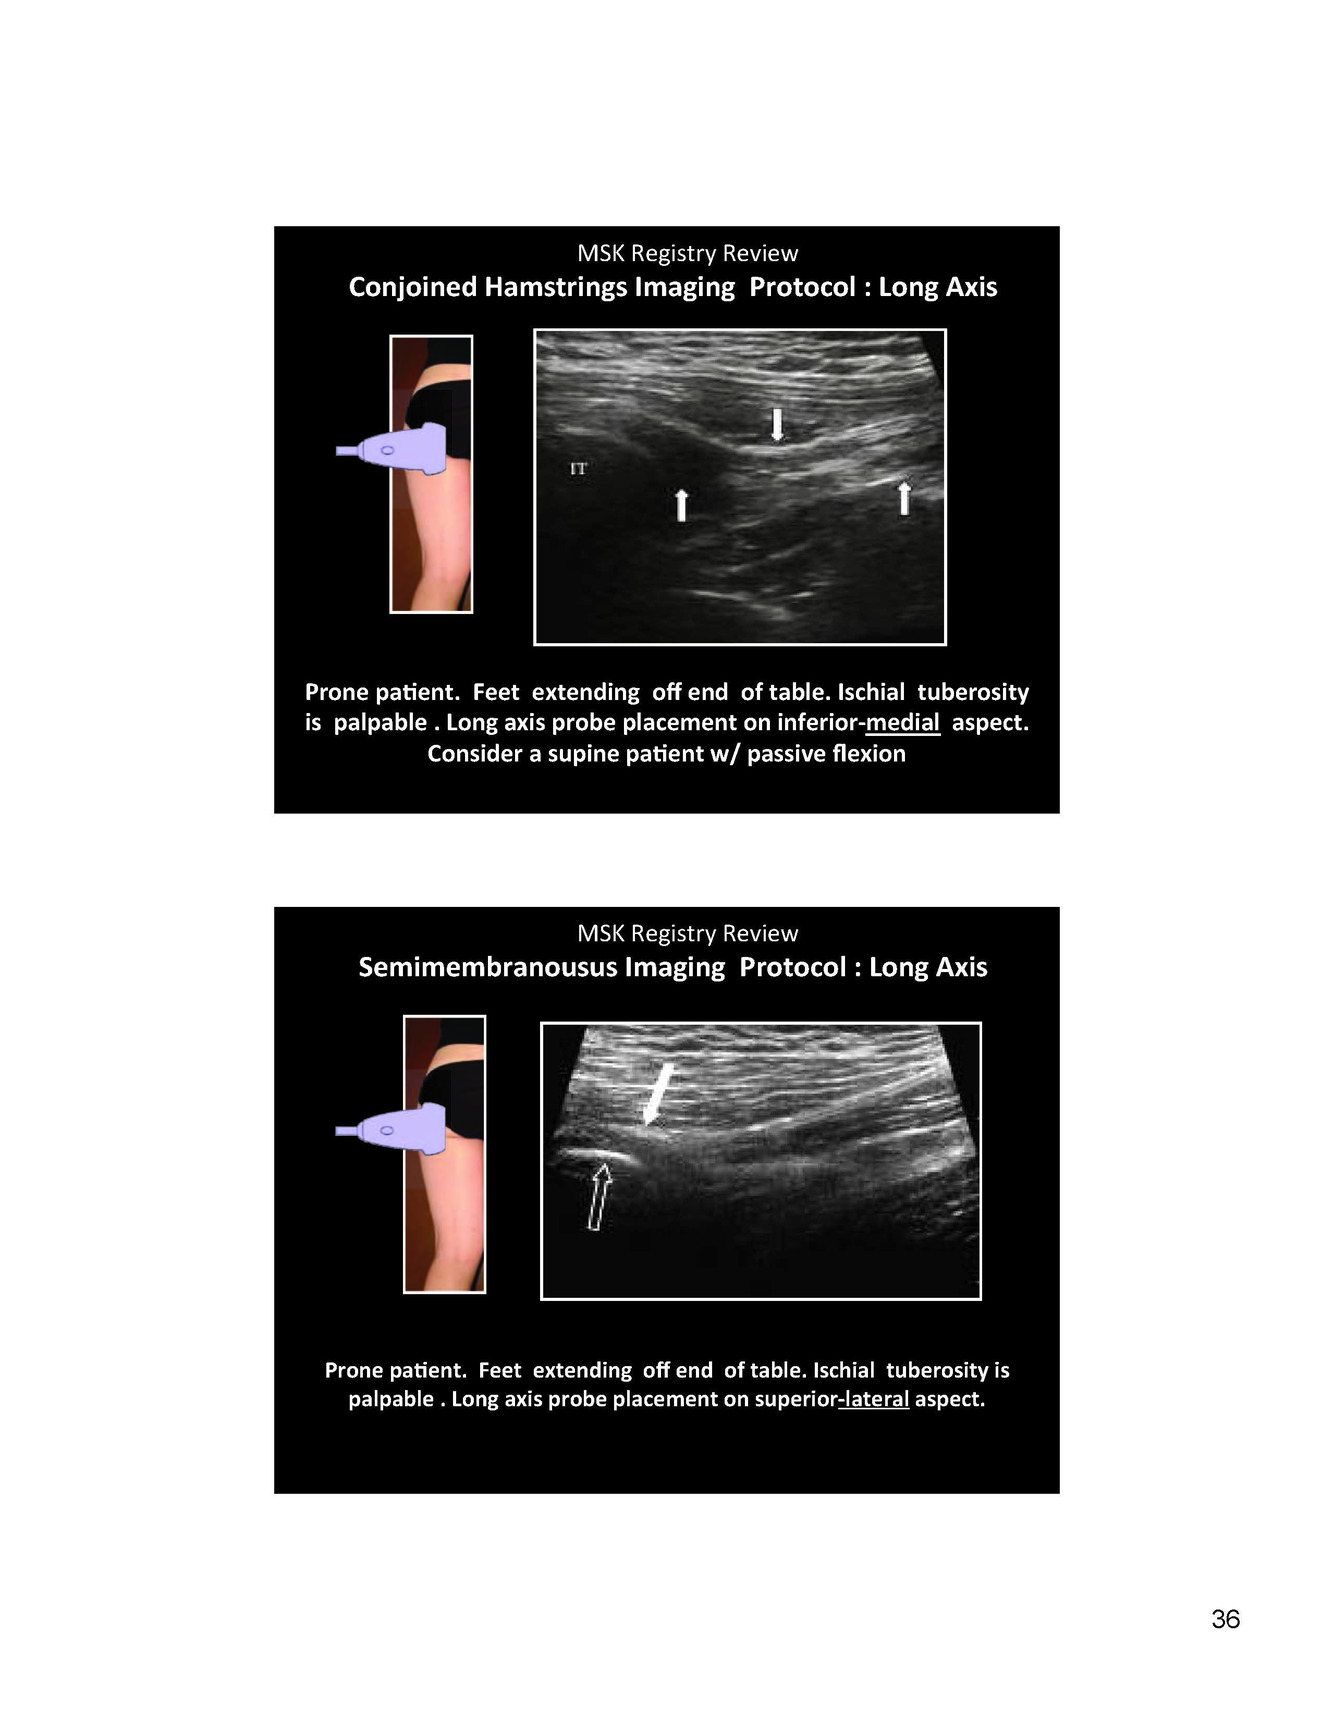

LFCN will require what for a nerve injection

proximity to the ASIS and medial to lateral in plane apporach